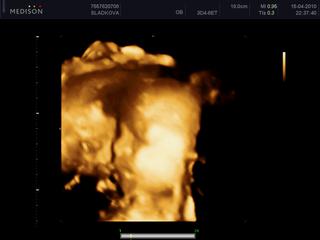

ahojte ... tak sme boli na tom 4D a nase druhe dieta bude asi zase introvert a hanblivec ... celu dobu malo tvaricku zaborenu do placenty, takze nemame skoro ziadne pekne zabery ... aj nozky drzalo pevne pri sebe, takze doktorka povedala len ze to naozaj vyzera na dievcatko, ale istota nie je 😉

tu je jedina fotka, kde je aspon co to vidno ... ani som tam nebola dlho, lebo to vyzeralo beznadejne na nejaky lepsi zaber, tak mi dala este jeden termin na buduci tyzden, ze to skusime, ci nebudeme mat stastie na lepsiu polohu 😉

denisse mala je zlatunka, mas nahodou peknu fotku a fajn doktorku, ze ti dala este termin...